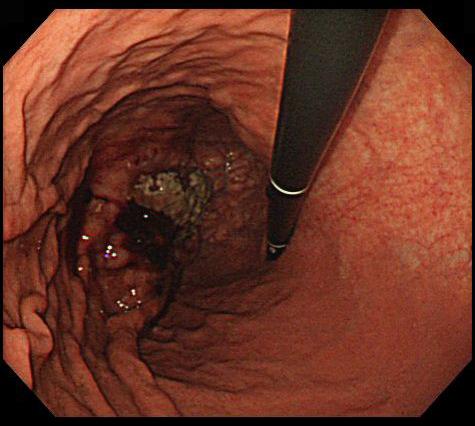

Criteria of Hist.ClassificationMalignant Lymphoma/Malignant lymphoma

LocationStomach/More than one of above

Technique, MethodEndoscopy

Size40 -

Depth of Tumor Invasionserosa (adventitia)